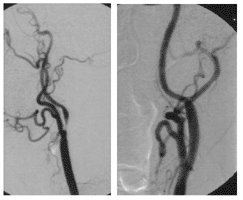

Abbildung:

Die Abbildungen A und B zeigen einen 67-jährigen Mann nach Stentimplantation in die linke Arteria carotis interna vor 2 Jahren.

Abb. B zeigt die CT Angiographie des Stents in der linken ACI, welcher regulär entfaltet und perfundiert ist.

Abb. A zeigt jedoch eine höchstgradige Stenose der ACI auf der rechten Seite (Pfeil).